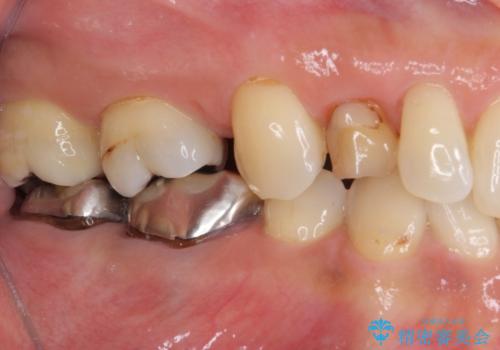

- 残存している乳歯や欠損部の隙間を気にして来院された患者様です。

上顎は左右ともに小臼歯が欠損しており、右側は乳前歯が残っている状態でした。

ブリッジによる補綴治療にて、欠損や隙間を補完することとしましたが、神経を取り除いたり、審美的に不自然になることを避けるため、部分矯正を併用することとしました。

乳歯は事前に抜歯することとしました。